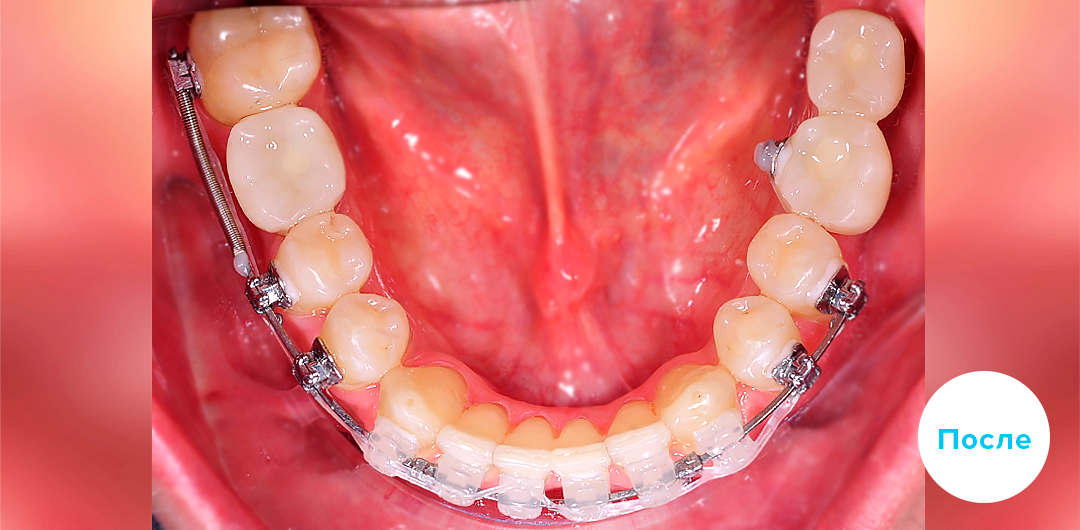

До

После

ЛЕЧЕНИЕ ДЕФИЦИТА МЕСТА НА ЧАСТИЧНОЙ БРЕКЕТ-СИСТЕМЕ У ДЕТЕЙ

Смотреть кейс